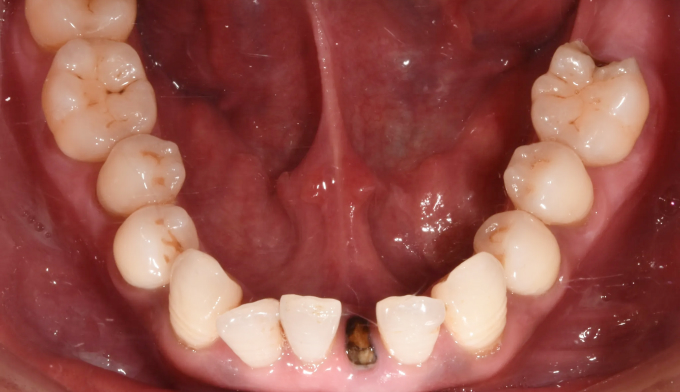

그동안 구강관리 소홀로 아래앞니 하나가 충치로 인해 소실되었으며, 동시에 골격의 주걱턱 경향으로 인해 앞니가 거꾸로 물리는 상황입니다. 아래앞니 빈공간을 임플란트나 크라운과같은 보철치료로 마무리 할 수도 있지만 교정치료를 통해 공간을 메운다면 동시에 거꾸로 물리는 앞니도 개선 가능하므로 교정치료가 보철치료보다 훨씬 효과적인 치료라고 볼 수 있습니다. 환자분의 교정치료에 대한 협조도와 이해도가 높아 비교적 이른 시간내에 교정치료가 마무리되어 매우 만족해 하셨던 케이스입니다. 총 교정기간은 14개월 소요되었습니다.